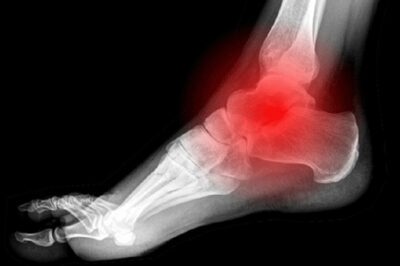

Trong các hoạt động thể thao như chạy, nhảy hoặc chơi các môn vận động mạnh, cổ chân thường xuyên chịu tác động lớn. Chính vì thế, các tình huống xoay hoặc lật cổ chân bất ngờ xảy ra khi chân không được chuẩn bị hoặc quá tải sẽ dễ dẫn đến chấn thương. Đây là nguyên nhân chính gây ra các dạng bong gân, rách dây chằng hoặc thậm chí gãy xương cổ chân.

Khi chân vị lệch khỏi quỹ đạo bình thường do xoay hoặc lật đột ngột, hệ thống dây chằng chống đỡ quanh cổ chân bị kéo giãn quá mức hoặc đứt rời, dẫn đến rối loạn cấu trúc của vùng cổ chân. Thường gặp trong những trường hợp người chơi thể thao nhanh chóng đổi hướng khi chạy hoặc nhảy mà không kiểm soát kịp thời, hoặc khi mặt sân trơn trượt, không ổn định, gây mất cân bằng. Những tình huống này đặc biệt nguy hiểm, vì nếu không xử lý đúng cách ngay từ ban đầu, có thể dẫn đến chấn thương nặng và kéo dài thời gian hồi phục.

Một dấu hiệu rõ ràng của chấn thương cổ chân là sự đau đớn tăng lên khi cố gắng xoay, gập hoặc duỗi cổ chân. Điều này cho thấy các cấu trúc như dây chằng, gân hoặc mô mềm quanh vùng bị ảnh hưởng, phản ứng với các chuyển động dài hạn hoặc bất ngờ.

Việc cảm nhận rõ rệt mức độ đau khi di chuyển hoặc vận động cổ chân giúp chẩn đoán sơ bộ về loại tổn thương, chẳng hạn như bong gân nhẹ, rách dây chằng hoặc tổn thương mô mềm sâu. Trong trường hợp này, các hoạt động bình thường như đi bộ, đứng hoặc chạy đều gây ra cảm giác đau nhói hoặc khó chịu, khiến người bệnh cảm thấy bất lực trong việc thực hiện các hoạt động hàng ngày.

Ngoài ra, cảm giác đau tăng lên rõ rệt khi cố gắng gập, duỗi hoặc xoay cổ chân không chỉ là dấu hiệu của việc tổn thương mô mềm mà còn cảnh báo mức độ nghiêm trọng cần phải can thiệp y tế ngay lập tức. Rất nhiều trường hợp có thể gặp phải các biến chứng nếu tự ý điều trị hoặc bỏ qua các triệu chứng này, dẫn đến các tổn thương mãn tính hoặc gây hạn chế vận động lâu dài.